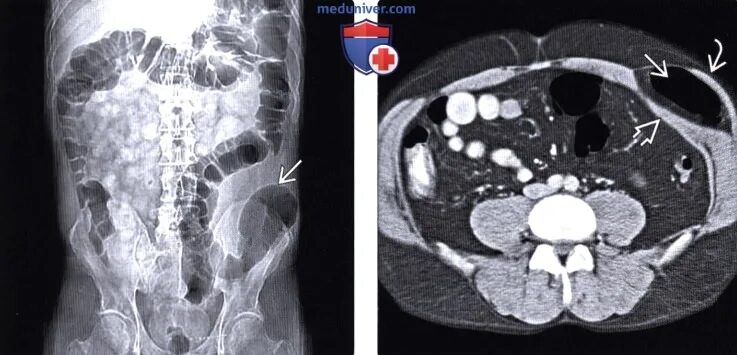

Грыжа спигелиевой линии